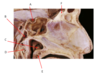

Which nerve is labeled by C?

Inferior alveolar

(Branch of CN V3)

A.

B. Chorda Tympani (branch of CN 7)

C. Inferior Alveolar n. (branch of CN 5.3)

D. Facial n. (CN 7)

E. Lingual n. (branch of CN 5.3)

F. Posterior Superior Alveolar n. (branch of CN 5.2)

G.

H.

I. Mental n.

Which nerve is labeled by F?

Posterior superior alveolar nerve

(Branch of CN V2)